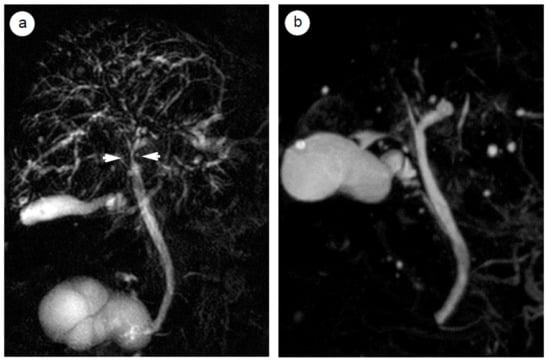

4.3. Radiological and Ultrasonographic Evaluation for Assessing AIP Response to Steroids

- Matsubayashi, H.; Yoneyama, M.; Nanri, K.; Sugimoto, S.; Shinjo, K.; Kakushima, N.; Tanaka, M.; Ito, S.; Takao, M.; Ono, H. Determination of steroid response by abdominal ultrasound in cases with autoimmune pancreatitis. Dig. Liver Dis. 2013, 45, 1034–1040. [Google Scholar] [CrossRef]

- Matsubayashi, H.; Uesaka, K.; Kanemoto, H.; Aramaki, T.; Nakaya, Y.; Kakushima, N.; Ono, H. Reduction of splenic volume by steroid therapy in cases with autoimmune pancreatitis. J. Gastroenterol. 2013, 48, 942–950. [Google Scholar] [CrossRef]

- Ishikawa, T.; Itoh, A.; Kawashima, H.; Ohno, E.; Itoh, Y.; Nakamura, Y.; Hiramatsu, T.; Miyahara, R.; Ohmiya, N.; Haruta, J.; et al. Peripancreatic vascular involvements of autoimmune pancreatitis. J. Gastroenterol. Hepatol. 2012, 27, 1790–1795. [Google Scholar] [CrossRef]